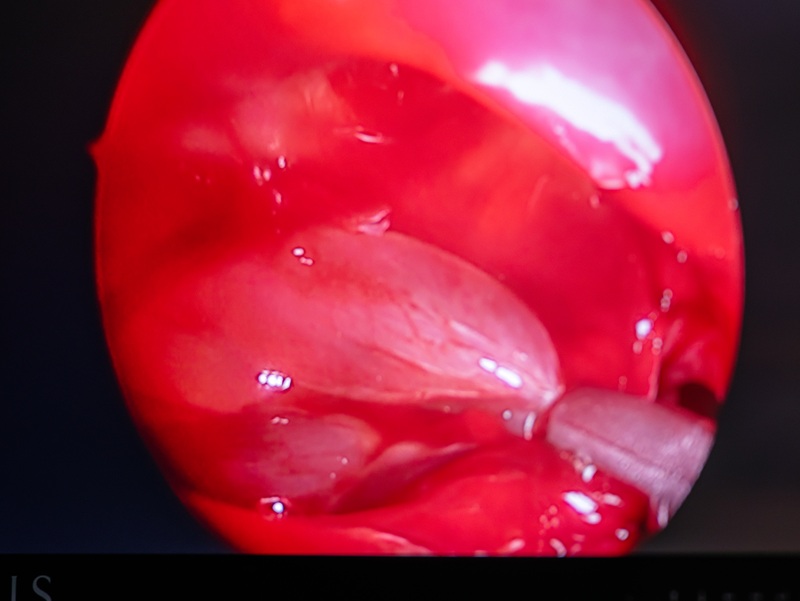

В современной отоларингологии применяются эндоскопические методики, обеспечивающие точность и минимальную травматизацию тканей. Одним из основных способов является удаление полипов носа шейвером, который позволяет аккуратно иссекать патологическую ткань с одновременной аспирацией, что уменьшает отек и ускоряет восстановление. При необходимости дополнительно используются биопсийные щипцы.

- введение эндоскопа в полость носа;

- визуализация полипов;

- аккуратное удаление патологической ткани шейвером или инструментами;